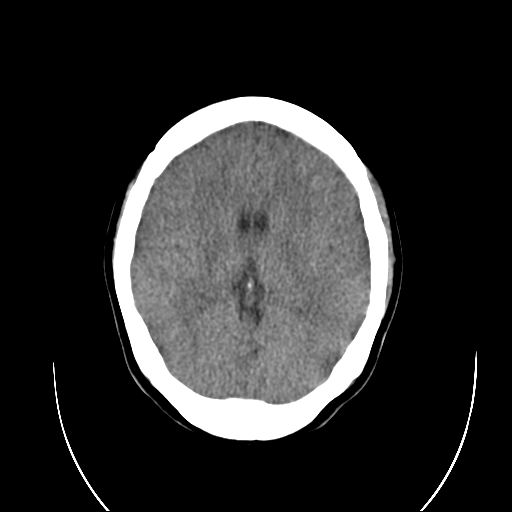

标题: CT18310:女,29岁,头部外伤后头疼、头晕十天。请会诊!! [打印本页]

标题: CT18310:女,29岁,头部外伤后头疼、头晕十天。请会诊!!

左顶叶裂隙样低密度灶,考虑什么呢??

请问 左顶叶低密度影  考虑什么呢???

个人认为诊断外伤性脑肿胀依据不足,首先是临床症状不太支持,第二是影像表现也不支持:年轻人脑室池可这样表现,弥漫性脑肿胀应有水肿导致的实质密度减低从而灰白质分界不清,而本例没有.至于左侧额叶后部裂隙样低密度影,考虑为脑沟,因与外侧脑沟相连.

个人认为诊断外伤性脑肿胀依据不足,首先是临床症状不太支持,第二是影像表现也不支持:年轻人脑室池可这样表现,弥漫性脑肿胀应有水肿导致的实质密度减低从而灰白质分界不清,而本例没有.至于左侧额叶后部裂隙样低密度影,考虑为脑沟,因与外侧脑沟相连.支持!建议短期复查!

左顶叶裂隙样低迷度灶,有人考虑:脑裂畸形。是否正确呢???

左顶叶裂隙状低密度影为脑沟影,影像表现不考虑脑肿胀